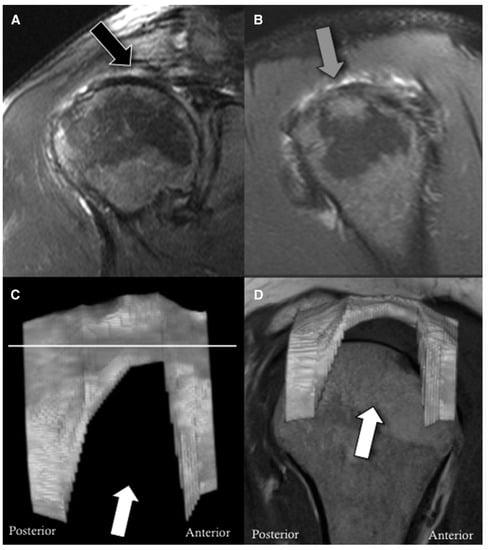

- Meyer, D.C.; Wieser, K.; Farshad, M.; Gerber, C. Retraction of Supraspinatus Muscle and Tendon as Predictors of Success of Rotator Cuff Repair. Am. J. Sports Med. 2012, 40, 2242–2247. [Google Scholar] [CrossRef]

- Gyftopoulos, S.; Beltran, L.S.; Gibbs, K.; Jazrawi, L.; Berman, P.; Babb, J.; Meislin, R. Rotator cuff tear shape characterization: A comparison of two-dimensional imaging and three-dimensional magnetic resonance reconstructions. J. Shoulder Elb. Surg. 2015, 25, 22–30. [Google Scholar] [CrossRef]